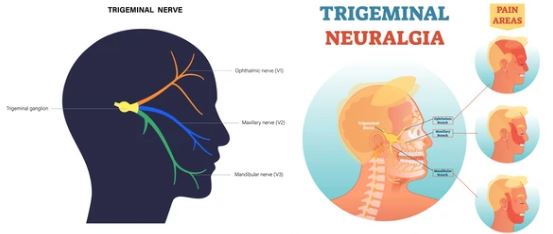

J Dent (Shiraz). 2024 Mar; 25(1): 17–25. Published online 2024 Mar 1. doi: 10.30476/dentjods.2023.95758.1889 PMCID: PMC10963861 PMID: 38544777 Efficacy of Laser Therapy in Trigeminal Neuralgia: a Systematic Review Sara Haghighat, DMD Student,1 Fahimeh Rezazadeh, DMD, MScD,2 Hossein Sedarat, MD Student,3 Amir

Study of the outcome of patients undergoing pulsed radiofrequency for the treatment of Trigeminal Neuralgia: An observational study. Neha Sharma, Iqra Nazir Naqash, Zulfiqar Ali, Nadeem Ahmad Khan, Ravouf P Asimi, Imtiyaz A

Noninvasive neuromodulation of supraorbital and occipital nerves as an adjunct to management of chronic headache Nazia Tauheed1, Aftab Hussain1, Hira Afzal1, Lubna Zafar2, Hammad Usmani1 1 Department of Anaesthesiology and Critical Care, Jawaharlal Nehru